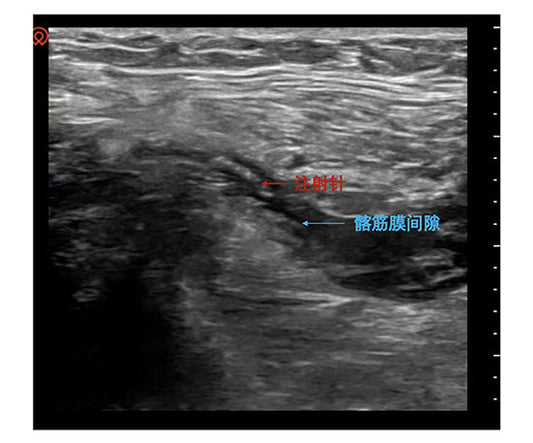

Pre-emptive Analgesia for Hip Fractures: How Beijing Tongren Hospital Reconstructs Safety Barriers for Ultra-Elderly Patients

Hip fractures are often termed the "last fracture of a lifetime" for the elderly. By advancing Fascia Iliaca Compartment Block (FICB) to the moment of admission, the Anesthesiology Department at...